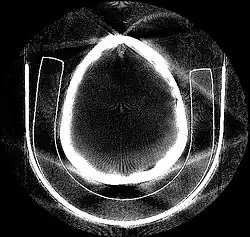

Deep learning methods are widely applied to image reconstruction nowadays and have achieved impressive results in various image reconstruction tasks, including low-dose denoising, sparse-view reconstruction, limited angle tomography and metal artifact reduction. An excellent overview can be found in the special issue [5] of IEEE Transaction on Medical Imaging. One group of deep learning reconstruction algorithms apply post-processing neural networks to achieve image-to-image reconstruction, where input images are reconstructed by conventional reconstruction methods. Artifact reduction using the U-Net in limited angle tomography is such an example application.[6] However, incorrect structures may occur in an image reconstructed by such a completely data-driven method,[7] as displayed in the figure. Therefore, integration of known operators into the architecture design of neural networks appears beneficial, as described in the concept of precision learning.[8] For example, direct image reconstruction from projection data can be learnt from the framework of filtered back-projection.[9] Another example is to build neural networks by unrolling iterative reconstruction algorithms.[10] Except for precision learning, using conventional reconstruction methods with deep learning reconstruction prior [11] is also an alternative approach to improve the image quality of deep learning reconstruction.